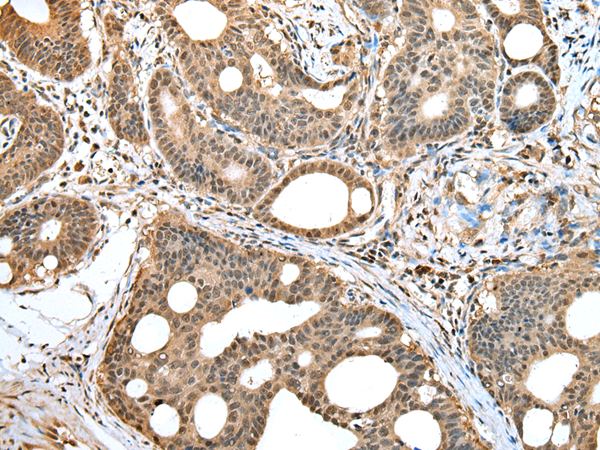

IHC positive control: |

Human gastric cancer and human tonsil |

IHC Recommend dilution: |

25-100 |